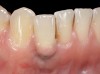

The following case report provides an example of this case scenario: A 28-year-old white female patient presented with her maxillary right lateral incisor significantly longer than the contralateral tooth following restoration of an existing crown that was 10 years old (Figure 3). The patient was dissatisfied with the esthetic appearance of the restoration due to the increased length, recession of the gingival tissues, and discoloration of the surrounding mucosa (Figure 4). Similar to case scenario No. 1, the first step in treatment was to decoronate the healthy implant by placing a flat surgical cover screw and employing a provisional resin-bonded-retained (RBR) prosthesis as a transitional fixed restoration (Figure 5 and Figure 6). The gingival augmentation in situ was allowed to take place for 2 to 3 weeks and was evaluated after that time (Figure 7).

Fig 5. A surgical cover screw was placed onto the implant in order to achieve gingival augmentation in situ prior to a secondary soft-tissue procedure.

Fig 6. A transitional resin-bonded-retained dental prosthesis was used to replace tooth No. 7.